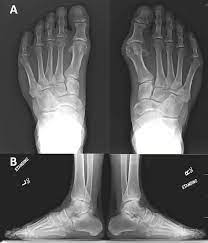

Gout In Extremis Massive Soft Tissue Tophaceous Deposits Springerlink

Gout In Extremis Massive Soft Tissue Tophaceous Deposits Springerlink from media.springernature.com